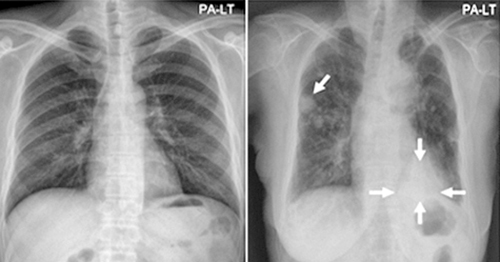

폐암은 흡연자의 경우 비흡연자보다 폐암이 발생할 가능성이 훨씬 높으며, 폐암이 무서운 이유는 사망률이 85퍼센트가 확진 후 5년 안에 사망할 정도로 높기 때문입니다. 폐암은 한국에서 두 번째로 흔한 암으로 아주 무서운 질환입니다. 말 그대로 폐의 악성종양을 뜻하고 장기간 흡연하는 흡연자에게 특히나 발병율이 높으며 최근에도 여러 환경적 요인에 의해 발병하며 있습니다.

폐암 초기증상 첫번째는 호흡곤란입니다.폐암 환자의 25퍼센트에서 나타나는 일반적인 증상으로 호흡곤란이 일어나는 이유는 다발성 폐전이가 폐 양쪽에서 관찰되는 경우 일어날 수 있으며 폐암과 거기에다가 악성 흉수가 같이 다가오게되는 경우 발생합니다. 평소와는 달리 숨이 차는 느낌이 들면서 숨을 들이쉬고 내쉴때 쌕쌕 거리는 소리나 나온다면 폐암 초기증상을 의심해 볼 수 있습니다.